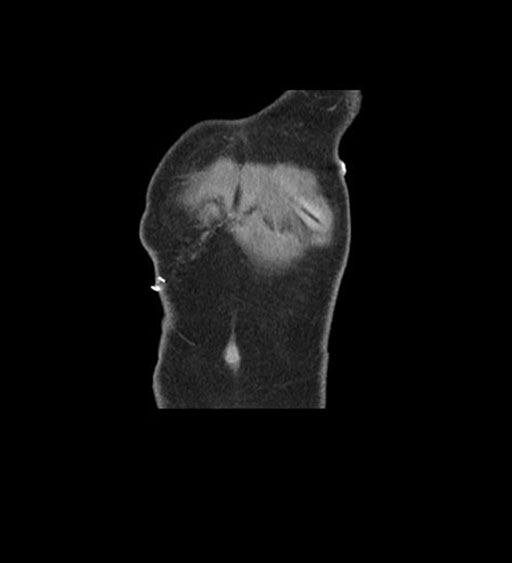

Coronal Arterial

Imaging analysis

Based on initial findings, which issue(s) would you be most concerned about?